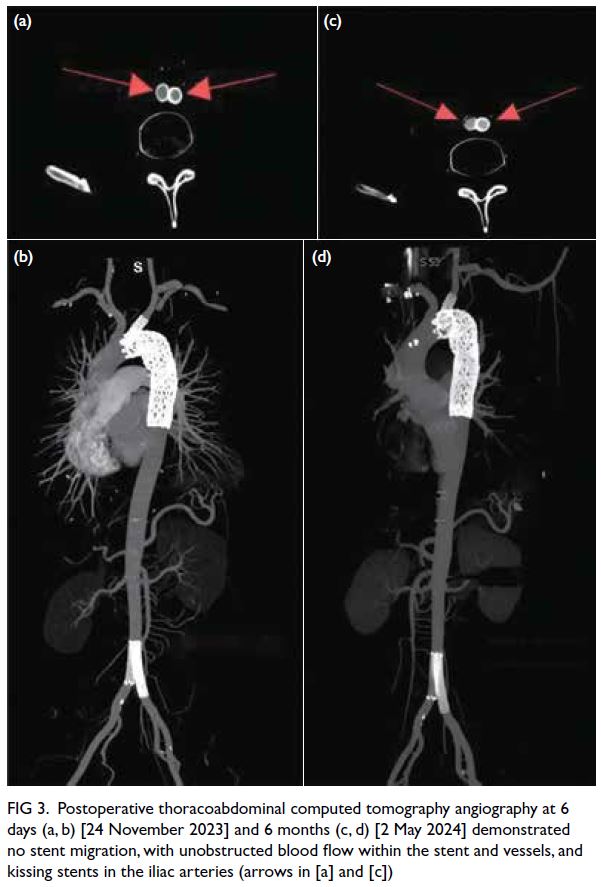

The patient improved and was discharged

1 week postoperatively. Follow-up computed

tomography angiography of the thoracoabdominal aorta at 6 days and 6 months postoperatively revealed

proper positioning of the stents, with unobstructed

blood flow within the stented vessels (Fig 3).

Figure 3. Postoperative thoracoabdominal computed tomography angiography at 6 days (a, b) [24 November 2023] and 6 months (c, d) [2 May 2024] demonstrated no stent migration, with unobstructed blood flow within the stent and vessels, and kissing stents in the iliac arteries (arrows in [a] and [c])